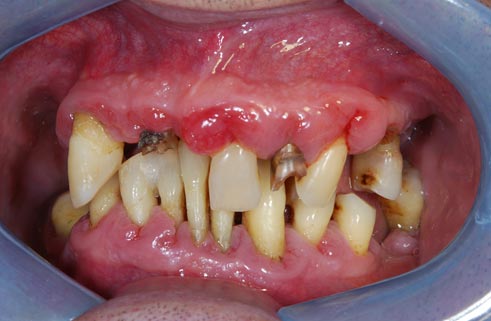

I denti irrecuperabili dell'arcata superiore ed inferiore del paziente di anni 65

sono stati sostituiti da 10 impianti, cioè protesi radicolari endo-ossee che sostengono le protesi fisse superiore ed inferiore.